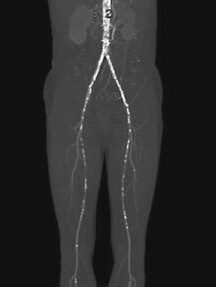

El hematoma intramural aórtico representa una entidad patológica en la que la sangre se acumula dentro de la capa media de la aorta, generalmente como consecuencia de hemorragia proveniente de…